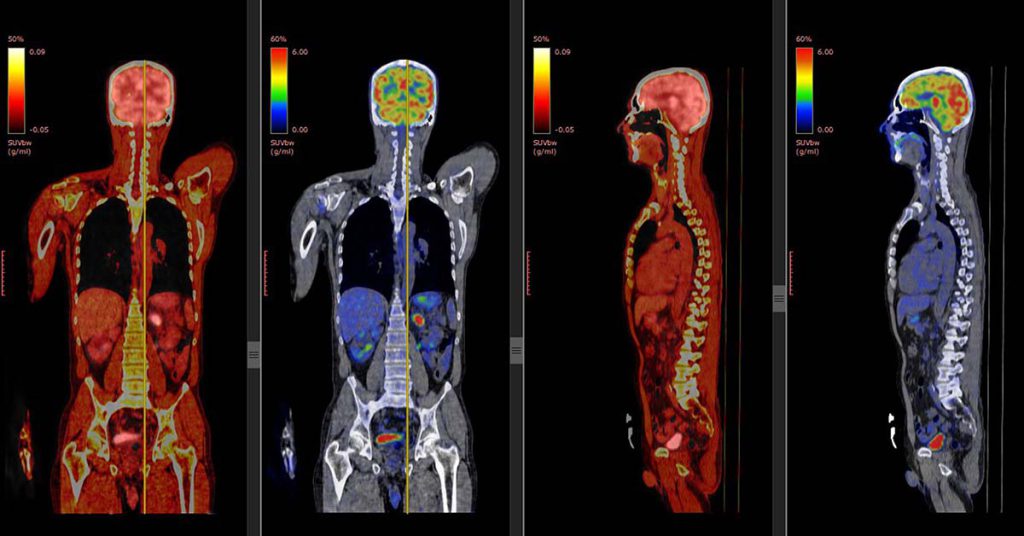

پت اسکن یا توموگرافی با گسیل پوزیترون (PET Scan)، یکی از پیشرفته ترین روش های تصویر برداری پزشکی است که با استفاده از مواد رادیواکتیو، فعالیت های متابولیکی بدن مانند جریان خون، سوخت و ساز سلول ها و عملکرد اندام ها را نشان می دهد.

برخلاف روش های ساختاری مثل MRI یا سی تی اسکن، پت اسکن عملکرد اندام ها را به تصویر می کشد و به پزشکان این امکان را می دهد تا سرطان، اختلالات مغزی، بیماری های قلبی یا عفونت های پنهان را با دقت بالا تشخیص دهند.

پت اسکن (Positron Emission Tomography) یکی از فناوری های پیشرفته تصویر برداری پزشکی است که کاربردهای فراوانی در تشخیص و مدیریت بیماری ها دارد. این روش با نشان دادن فعالیت متابولیکی سلول ها، تصویری دقیق تر و عملی تر از عملکرد اندام ها و بافت ها ارائه می دهد. مهم ترین کاربردهای پت اسکن عبارت اند از:

- پت اسکن میتواند تومورها را در مراحل اولیه شناسایی کرده و میزان گسترش بیماری را مشخص کند.

- با بررسی فعالیت متابولیکی تومورها، پزشکان میتوانند اثر درمان هایی مثل شیمی درمانی و پرتودرمانی را ارزیابی کنند.

- پت اسکن جریان خون و عملکرد عضله قلب را بررسی می کند و در تشخیص آسیب های قلبی موثر است.

- این روش در بررسی بیماری هایی مانند آلزایمر، پارکینسون و صرع کاربرد دارد.

- پت اسکن میتواند نواحی عفونی یا التهابی را در بدن شناسایی کند.

امروزه تجهیزات پزشکی به سرعت در حال پیشرفت هستند و معتبرترین مراکز PET/CT تهران نیز با استفاده از دستگاه های به روز و پیشرفته، دقت و کیفیت تشخیص را به طور چشمگیری افزایش داده اند. دستگاه های جدید پت اسکن دارای رزولوشن بالا، نویز کم و قابلیت کاهش دوز پرتوی دریافتی بیمار هستند که علاوه بر افزایش ایمنی، تصاویر دقیق تری از وضعیت متابولیکی بدن ارائه میدهند.

بسیاری از مراکز پیشرفته در تهران از دستگاههای PET/CT رده بالا استفاده میکنند که مزایای زیر را دارند:

- دقت تصویربرداری بالا تا ۹۵٪ یا بیشتر (خصوصاً برای تشخیص اولیه سرطان و مرحلهبندی آن)

- کاهش دوز رادیودارو برای به حداقل رساندن تابش به بدن

- قابلیت به کارگیری فناوریهای جدید مانند Time-of-Flight (TOF) برای جزئیات بیشتر بر روی تصاویر پزشکی